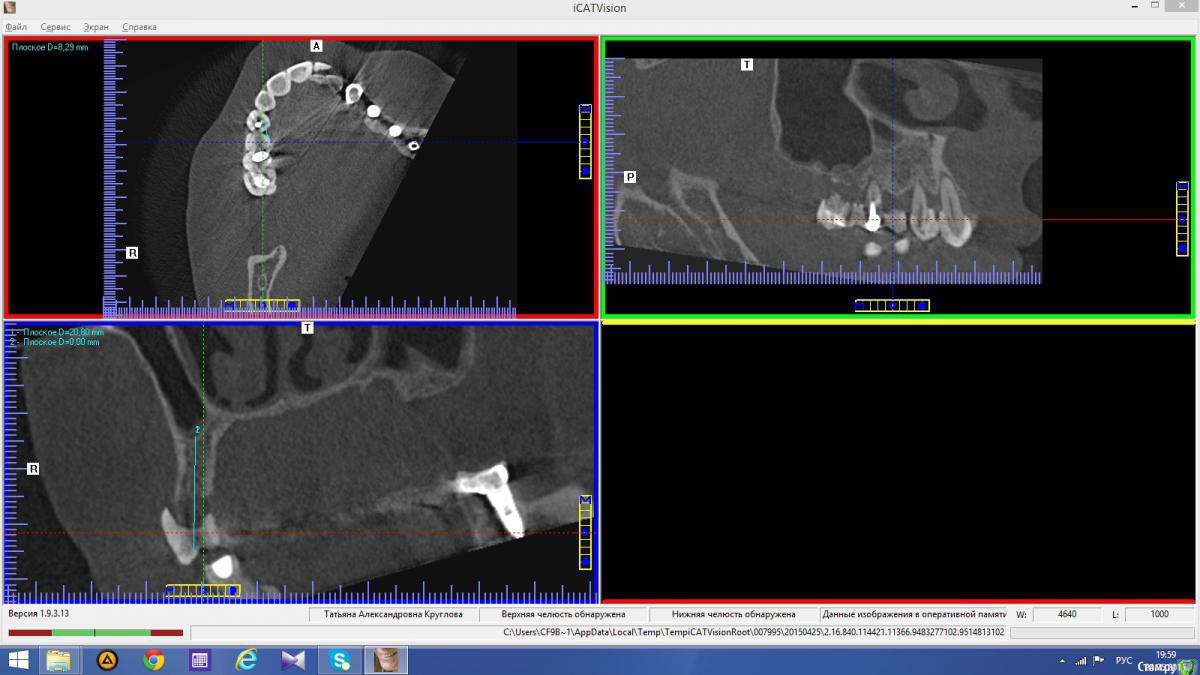

anvladd Опубликовано 24 ноября, 2015 Поделиться Опубликовано 24 ноября, 2015 Снимки не могли бы показать? Ссылка на комментарий

Abuk Опубликовано 24 ноября, 2015 Автор Поделиться Опубликовано 24 ноября, 2015 Снимки не могли бы показать? .все что есть готовое. Ссылка на комментарий

Abuk Опубликовано 24 ноября, 2015 Автор Поделиться Опубликовано 24 ноября, 2015 (изменено) Радикально Вы. Что оставили ей после имплантации-это инд аббатменты? На них мокап одели и нагрузили сразу? У всех был торк хороший? Или это временные абб? Что за систему использовали? В планах консоль назад, правильно я понимаю?Спасибо.увидев такую работу,сам так же подумал бы). Но там подвижность 2-3 ст. ближе к 3. Мосты болтались ,2 ки в хлам. 1 ки только стабильны. Снимал мосты,проводил кюретаж. Решил дернуть.Абатманы временные, тех. сделал на них коронки. Система анкилоз. Работа,на посл. фото, постоянная . Имплы в области 4 и по одному моляру ,консоли. Мок ап был до имплантации . По нему шаблон. Стабильность 15 -20 на 23 , остальное больше 30. Изменено 24 ноября, 2015 пользователем Abuk 1 Ссылка на комментарий